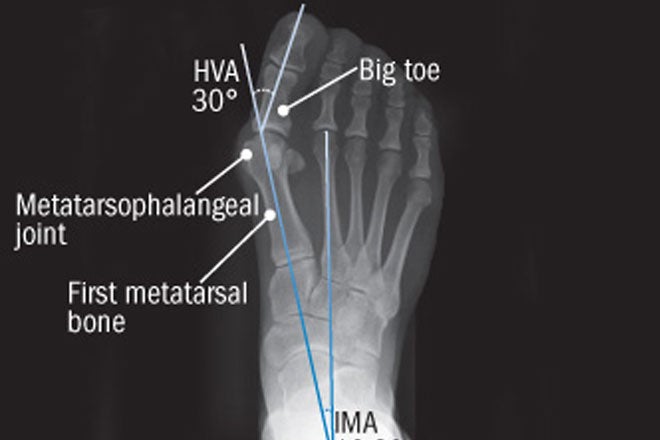

- Foot reconstruction surgery repairs bone fractures and foot deformities in children and adults.